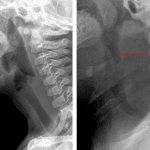

Age: 8 months

Sex: Female

Indication: Fever, drooling

Findings

- Marked thickening of the retropharyngeal soft tissues measuring up to 2 cm in thickness at the level of C2

Diagnosis

- Retropharyngeal abscess

Marked thickening of the retropharyngeal soft tissues measuring up to 2 cm in thickness at the level of C2, concerning for retropharyngeal edema and/or abscess. Consider contrast-enhanced neck CT for further evaluation.

Normal appearance of the epiglottis.

No ballooning of the hypopharynx.